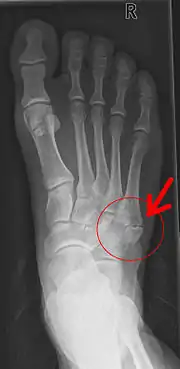

Pseudarthrose de la base du 5e métatarsien après un arrachement osseux.